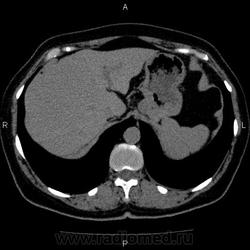

- https://radiomed.ru/sites/default/files/styles/case_slider_image/public/user/5278/10003_0.jpg?itok=VKMojSj8

Это кальцификация. Бывшая гематома, бывший воспалительный процесс, паразитарное поражение, гемангиома, сосудистая мальформация, злокачественное нечто либо метастаз. Без клиники, пола, возраста и болюсного КТ... ну допустим, я поставлю на солитарный метастаз. И это 50/50, т.е. либо я права, либо нет.

Натив без болюса, что обзорная урограмма без внутривенной.

гидативную нежизнеспособную кисту. Гемангиома гиподенсна относительно здоровой паренхимы, да и гематома так выглядеть не может.

На эхинококковую кисту похожа

Похоже на кальцинированную эхинококковую кисту печени; для уточнения КТ с болюсным мультифазным контрастированием; консультации гастроэнтеролога и онколога.

"Образование" 3 года без динамики. На УЗИ написали гемангиому. Спасибо всем.